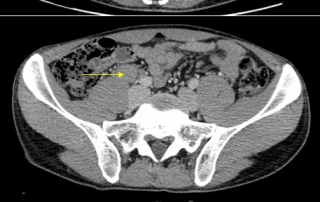

Hémogramme normal, VS 52 mm 1ère heure, albumine 38 g, bilan hépatique normal.

Biopsie médullaire normale.

L’atteinte sus-claviculaire est le site révélateur d’une atteinte initiale sous-diaphragmatique, sans atteinte médiastinale. L’imagerie explique l’atteinte initiale inguinale droite, puis l’extension lymphatique iliaque et latéro-aortique et inter aortico-cave. L’extension lymphatique sus-diaphragmatique passe par les ganglions du diaphragme et la chaine mammaire interne, puis latéro-trachéale. Le risque d’atteinte hépatique existe, en cas d’extension lymphatique au pédicule hépatique. Le risque d’atteinte splénique par voie hématogène est plus tardif (absence de voies lymphatiques afférentes à la rate)